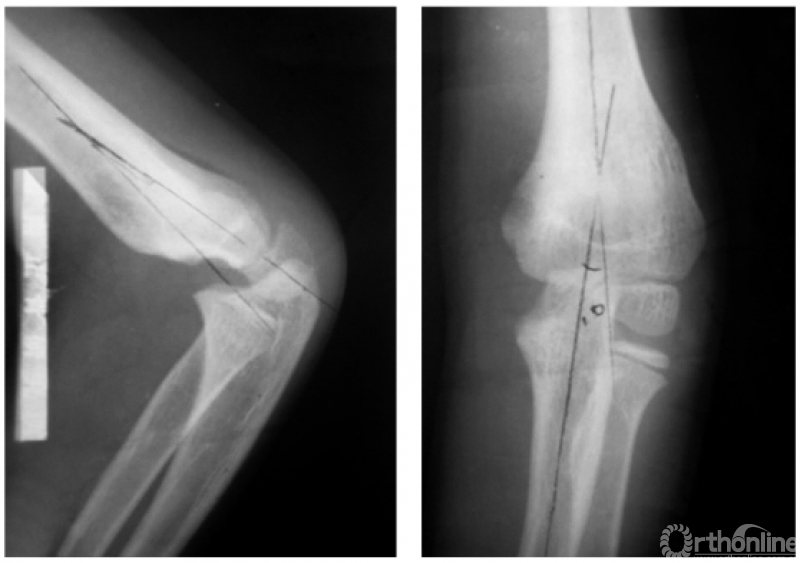

例3:伸展型兼尺偏并上尺桡关节脱位,即远折端向后、向内移位并上尺桡关节分开(图4)。

图4

例4:伸展型兼桡偏并肱骨内上髁Ⅱ度折,即远折端向后、向外移位,并内上髁骨块移至尺肱关节水平(图5)。

图5